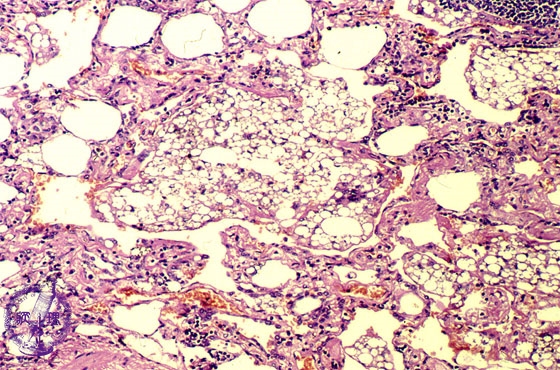

- (14)Lipoid pneumonia

Microscopic view (HE stain, Middle-power-view): Lipid and cholesterol crystal laden macrophages are seen within alveoli and alveolar septa accompanied by an inflammatory cell infiltrate.